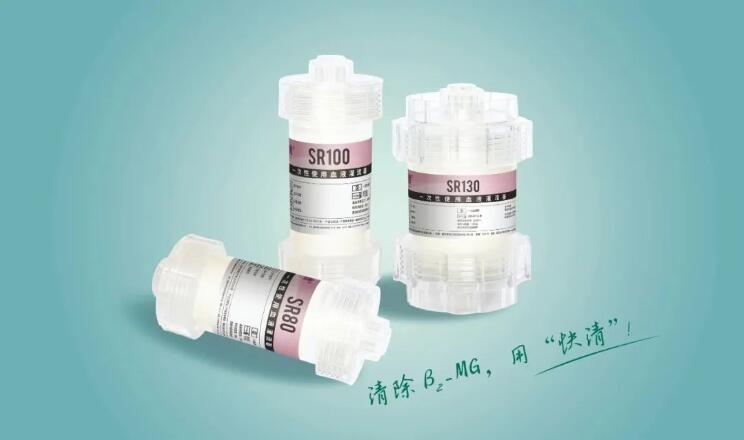

树脂血液灌流器-SR100

SR系列

树脂血液灌流器-SR100

快清®树脂炭血液灌流器

树脂血液灌流器-SR120

SR系列

树脂血液灌流器-SR120

快清®树脂炭血液灌流器

树脂血液灌流器-SR130

SR系列

树脂血液灌流器-SR130

快清®树脂炭血液灌流器